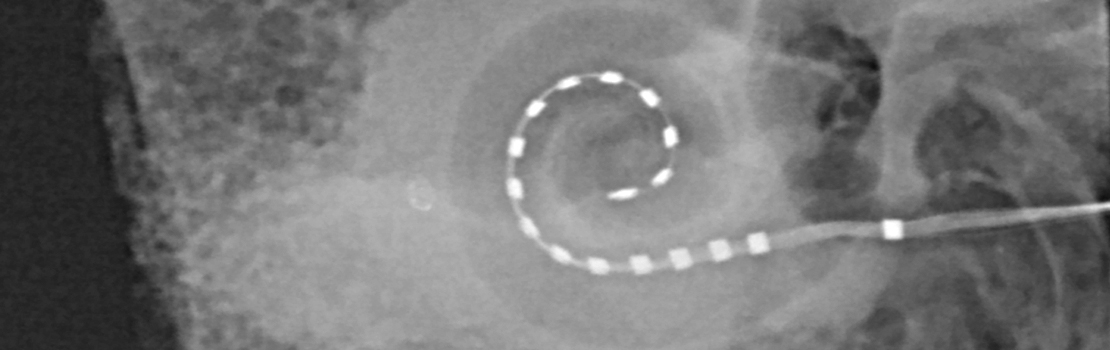

Cochlear植入器外声处理器连接插入cochlea电极阵列

术后图像电极插入cchlea